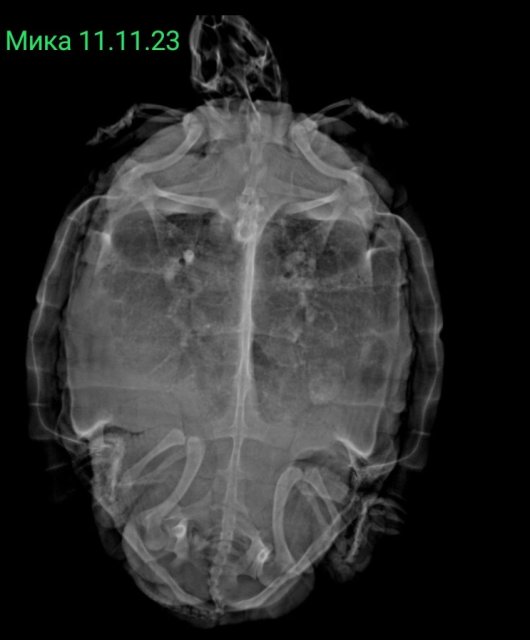

Собрала все её рентгены в кучу. Что можно сказать по последним двум, от 18 июня?

Screenshot_2025-06-23-20-49-43-211_com.vkontakte.android-edit.jpg

Screenshot_2025-06-23-20-44-46-266_com.miui.gallery-edit.jpg

Screenshot_2025-06-23-20-07-36-244_com.miui.gallery-edit.jpg

Screenshot_2025-06-23-20-06-00-118_com.android.chrome-edit.jpg